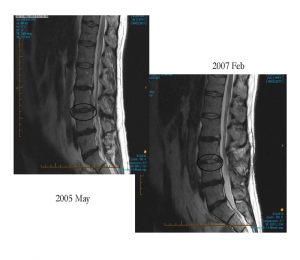

You can see in the below image the changes seen pre and post introduction to chair-care exercise. The increase uptake of water in these MRIs seen in L3-4 is thought to be due to regular off-loading of the discs. The patient reported doing the exercise 7 times a day. It is always nice to work with motivated patients as they are compliant and do listen to what a doctor suggests. I would consider this regeneration because of the re-introduction of water into the disc.